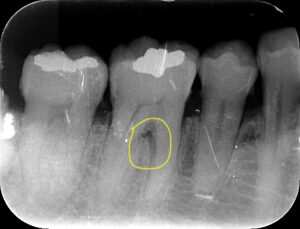

レントゲンですが黄色の部分、根分岐部と呼ばれていますが

歯槽骨が吸収しているため、黒く写っています。